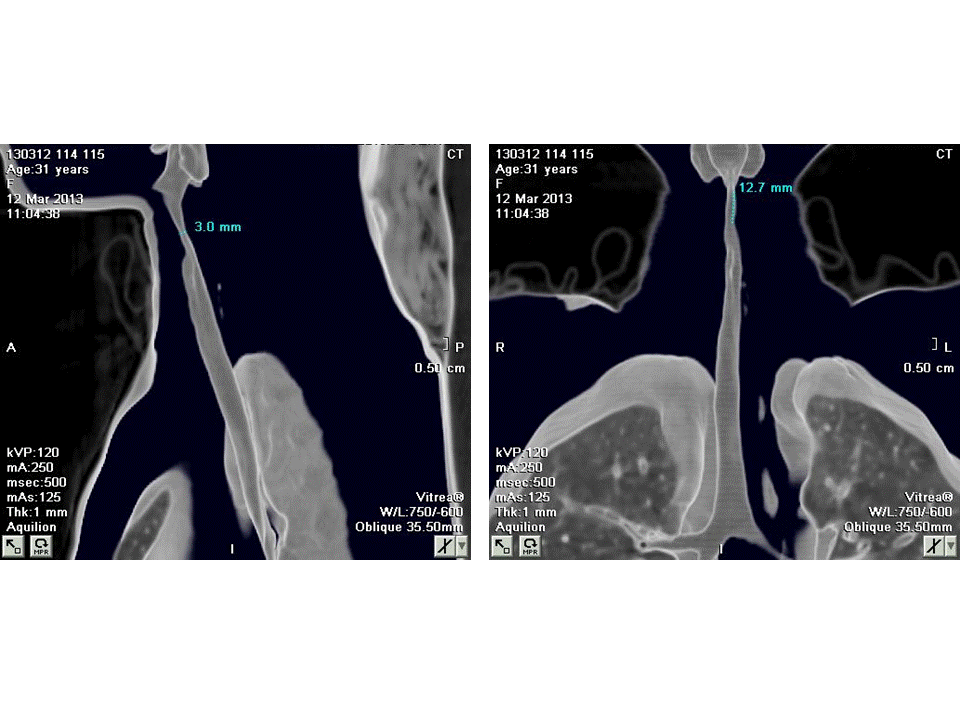

Tracheobronchomalacia Ct . Acquired tracheomalacia is a common finding, seen in approximately 10% of ct and up to 23% of autopsy and bronchoscopy series 5. There is increasing recognition of tracheobronchomalacia (tbm) in patients with respiratory complaints, though its true. Learn about tracheobronchomalacia (tbm), a condition where your airways collapse and close down, causing breathing problems. Tracheomalacia (tm) refers to weakness in the airway wall resulting in excessive airway narrowing during expiration. A dynamic ct scan of the trachea and carina confirmed expiratory airway collapse that was more marked on the left (see fig. Tracheobronchomalacia (tbm) refers to airway collapse due to typically excessive posterior membrane intrusion and.

There is increasing recognition of tracheobronchomalacia (tbm) in patients with respiratory complaints, though its true. Tracheobronchomalacia (tbm) refers to airway collapse due to typically excessive posterior membrane intrusion and. Acquired tracheomalacia is a common finding, seen in approximately 10% of ct and up to 23% of autopsy and bronchoscopy series 5. Learn about tracheobronchomalacia (tbm), a condition where your airways collapse and close down, causing breathing problems. Tracheomalacia (tm) refers to weakness in the airway wall resulting in excessive airway narrowing during expiration. A dynamic ct scan of the trachea and carina confirmed expiratory airway collapse that was more marked on the left (see fig.

Tracheobronchomalacia Ct Tracheobronchomalacia (tbm) refers to airway collapse due to typically excessive posterior membrane intrusion and. Acquired tracheomalacia is a common finding, seen in approximately 10% of ct and up to 23% of autopsy and bronchoscopy series 5. Tracheobronchomalacia (tbm) refers to airway collapse due to typically excessive posterior membrane intrusion and. There is increasing recognition of tracheobronchomalacia (tbm) in patients with respiratory complaints, though its true. Learn about tracheobronchomalacia (tbm), a condition where your airways collapse and close down, causing breathing problems. A dynamic ct scan of the trachea and carina confirmed expiratory airway collapse that was more marked on the left (see fig. Tracheomalacia (tm) refers to weakness in the airway wall resulting in excessive airway narrowing during expiration.